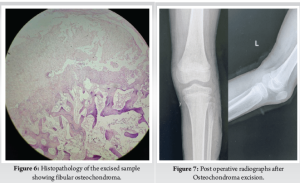

Under spinal anesthesia, the patient is placed supine with a sandbag placed underneath the affected buttock and a tourniquet was inflated after exsanguination. An 8 cm linear incision was taken just posterior to the fibula, along the line of the biceps femoris tendon and after a superficial surgical dissection, CPN was visualized. The nerve was mobilized and it was retracted anteriorly using a rubber drain tube. Muscles were stripped and fibula was exposed. En-block tumor excision was performed. Closure was done in layers followed by the above knee splint was given in an ankle neutral position. Excision of osteochondroma was done carefully thus relieving pressure followed by perineural neurolysis of CPN (Fig. 5). Gross specimen size was 2.4 cm X 1.5 cm X 1.5cm and histopathological examination confirmed the swelling as osteochondroma (Fig. 6) with no

evidence of any malignant transformation. Post operative x-rays revealed the removal of the osteochondroma and loss of the bony contour which could be the possible reason for compression of CPN (Fig. 7). The patient had an uneventful surgery and postoperative rehabilitation protocol initiated along with foot drop orthosis. Patient eventually gained full power 5 months after the procedure and was able to perform the activities of daily living. After 2 years of follow up, he has full functional and neurological recovery.